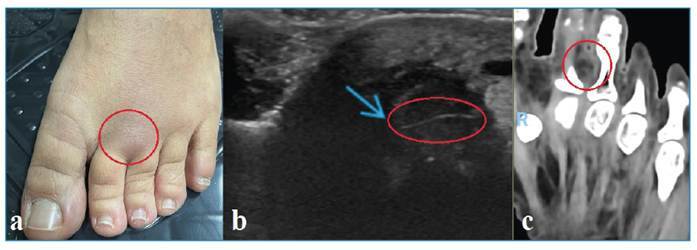

Diagnosis of larval migration using imaging tests.

利用影像学检查诊断幼虫迁移。